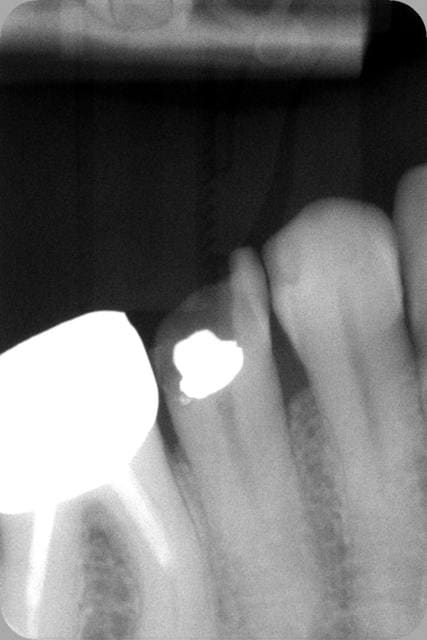

Voilà les radios : l'endo à l'amalgame dans la chambre de mon confrère (On notera aussi la belle endo sur la 6, courbure bien négociée par le confrère. Comment défendre ce type de boulot sur les 2 dents ?) et mon endo+RMIPP+compo à 139,70€.

Oui c'est pas au bout radiologiquement. A 80 ans c'est pas large, ça butait à la C+ 8/10èmes.

Le tenon fibré c'est la zone radioclaire au dessus, noyé dans le composite. On voit qu'il n'y a pas de gutta ni de ciment qui débordent.